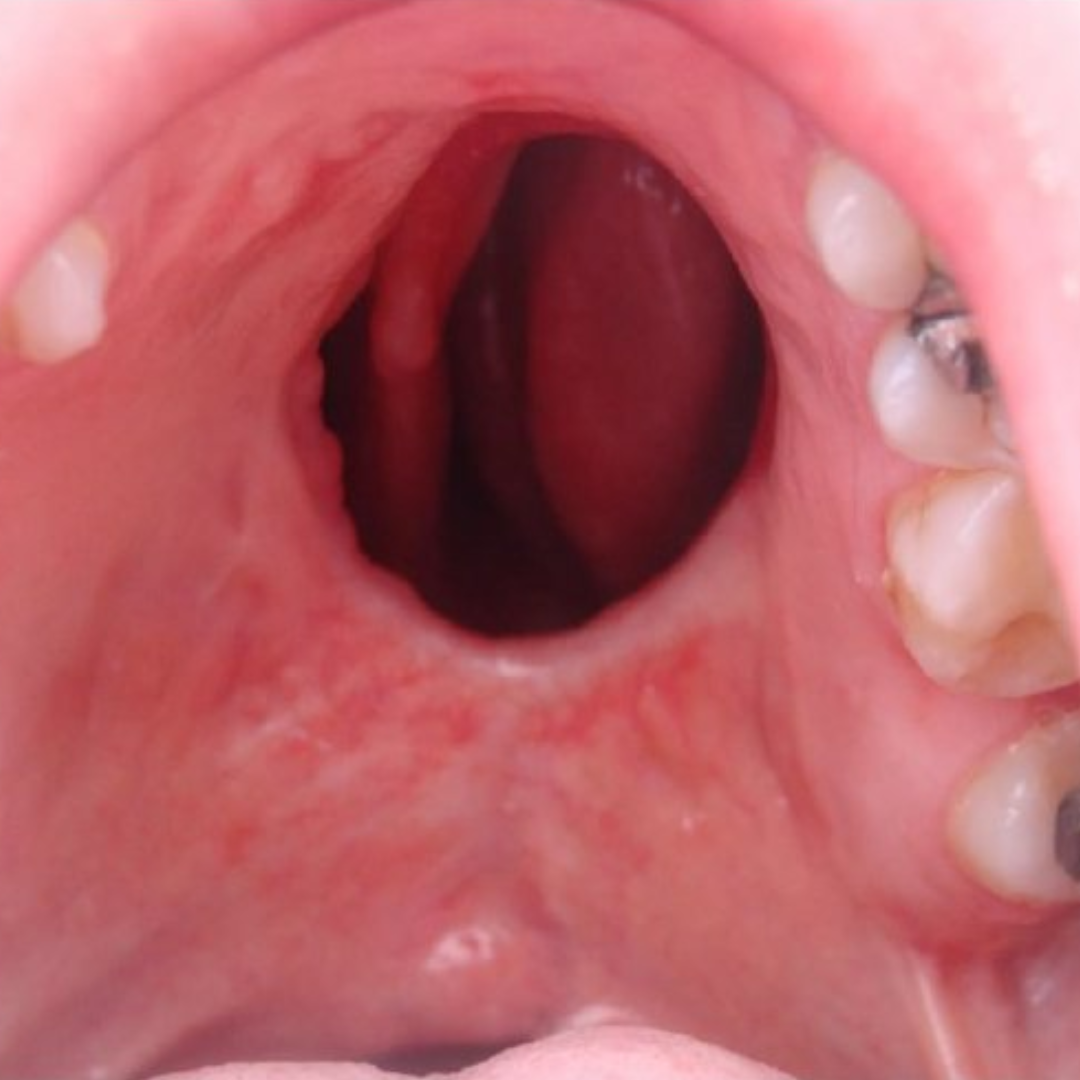

Cleft surgery involves reconstructive procedures to correct congenital openings in the upper lip and/or roof of the mouth, which develop during early pregnancy.

We offer advanced cleft lip and palate surgeries focused on restoring both function and appearance. Our procedures help improve feeding, speech, breathing, and facial symmetry—giving children and families a better quality of life. Every surgery is performed with precision, compassion, and personalized care.

Cleft lip repair is usually done between 3–6 months of age, and cleft palate surgery is typically performed between 9–18 months. The exact timing depends on the child’s health and individual needs.

Your child will be under general anesthesia during the procedure and will not feel pain during surgery. Post-operative discomfort is managed with child-safe pain relief and close monitoring to ensure a smooth recovery.